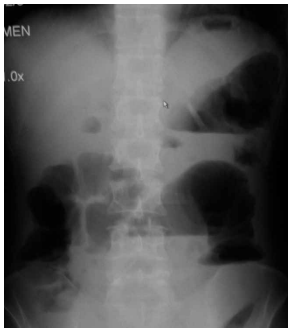

Paciente do sexo masculino, de 72 anos, portador de

diabetes mellitus do tipo 2 e doença renal crônica no

estágio 3b, apresenta história de dor abdominal e vômitos há 24 horas. Ao exame físico: PA: 82 × 48 mmHg;

FC: 122 bpm; FR: 28 irpm; SpO2: 94% com cateter nasal

de O2: 2 L/min; TAx: 38,9 ºC; TEC: 5 s; pele fria. Exames laboratoriais iniciais: lactato: 4,8 mmol/L; leucócitos:

18.000/mm3; creatinina: 2,3 mg/dL (baseline: 1,6). Depois

de administrados 30 mL/kg de cristaloide (1,8 L), o paciente evolui com PA média < 65 mmHg. Realizou radiografia de abdome no leito da UTI, mostrada a seguir:

(Arquivo pessoal; imagem usada com autorização)